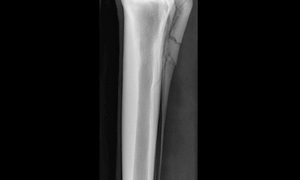

脛骨軟骨形成不全症 ~ 自発的な脚の骨折、壊死、および重度の疼痛と跛行に苦しみます

脛骨軟骨形成不全症(TD)は、脛骨の近位端での異常な軟骨の発達を伴う骨格骨障害です。これは主にブロイラー(コーニッシュ種)の自由給餌下で発生します。雄のニワトリは雌よりも脛骨軟骨形成不全症を発症する傾向があります。ほとんどの場合、生後3~8...